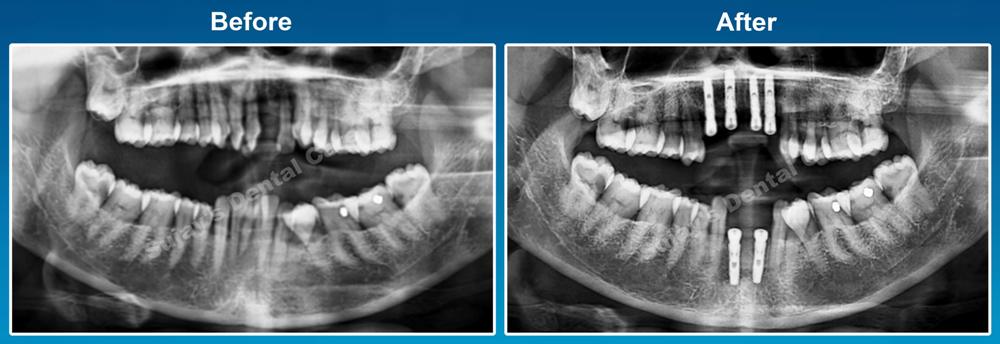

As a part of Evidence-based treatment, we took full mouth OPG. After examining OPG x-ray of the teeth, our team of dentists decided for

- Extraction i.r.t. 11,12,13,22,31,32,41.42.

- Followed by implant i.r.t. 11,13,21,22,31,41.

- Followed by implant supported fixed partial denture.